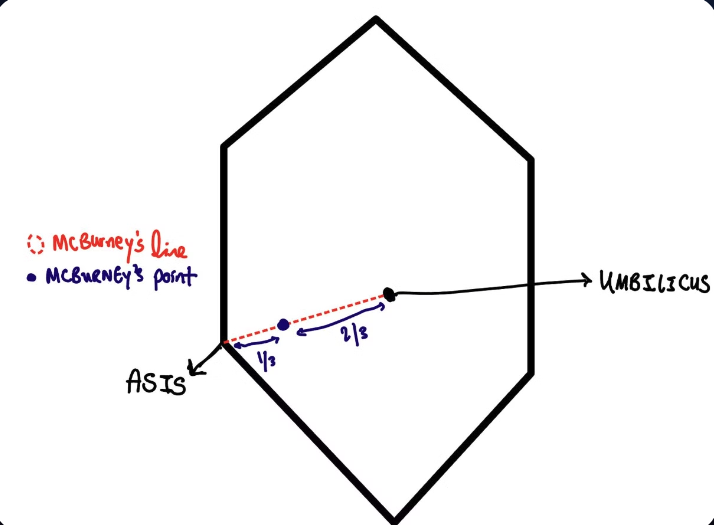

The base of the appendix classically lies at a point that lies 1/3 of the distance laterally on a line drawn between the umbilicus and the right ASIS (Anterior Superior Iliac Spine).

Diagram depicting the position of McBurney's point.

McBurney’s point:

- A point found 2/3 of the length of a line drawn from the umbilicus to the right ASIS. Pain at palpation of this point makes a patient “McBurney’s positive.”

Diagram depicting McBurney's point

Image depicting Mcburney's line and McBurney's point

Choose between McBurney's/Grid iron incision or Lanz incision based on surgeon preference.

- McBurney’s/Grid iron incision:

- an incision perpendicular to the line that forms McBurney’s point.

- how to locate

- find Mc Burney’s line (a line between ASIS and the umbilicus).

- how to locate

- an incision perpendicular to the line that forms McBurney’s point.

Diagram depicting McBurney's point

- Find McBurney’s point (a point 1/3 from the ASIS on this line)

Diargram depicting McBurney's point

- Gridiron incision: Draw a line perpendicular to McBurney’s line, bisecting McBurney’s line at Mc Burney’s point.

Gridiron incision

- Lanz incision

- a line through McBurney’s point.

- More transverse in comparison to the Gridiron incision (try to follow the skin creases)

- follow’s langer’s lines more closely, better. cosemsis

Lanz incision